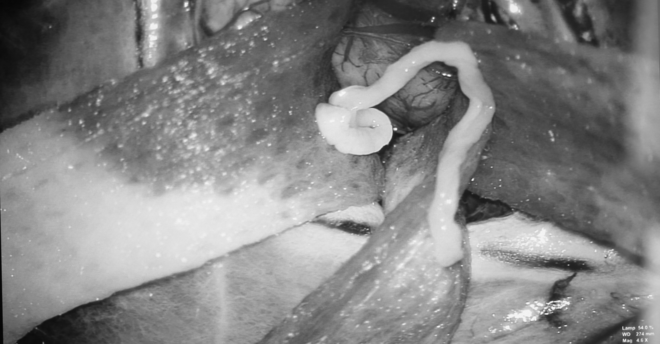

Ca phẫu thuật gắp sán nhái trong não bệnh nhân. Ảnh: VOV. |

Chụp cộng hưởng từ sọ não, các bác sĩ chẩn đoán ông A. có tổn thương choán chỗ vùng vỏ não vận động có thể do u hoặc nang ký sinh trùng trong não. Đến khi phẫu thuật, các bác sĩ mới xác định chính xác bệnh lý của A. là do u nang ký sinh trùng trong não dài 7 cm và tiến hành lấy ra.

Sán nhái dài 7 cm trong não người đàn ông. Ảnh: Vnexpress. |